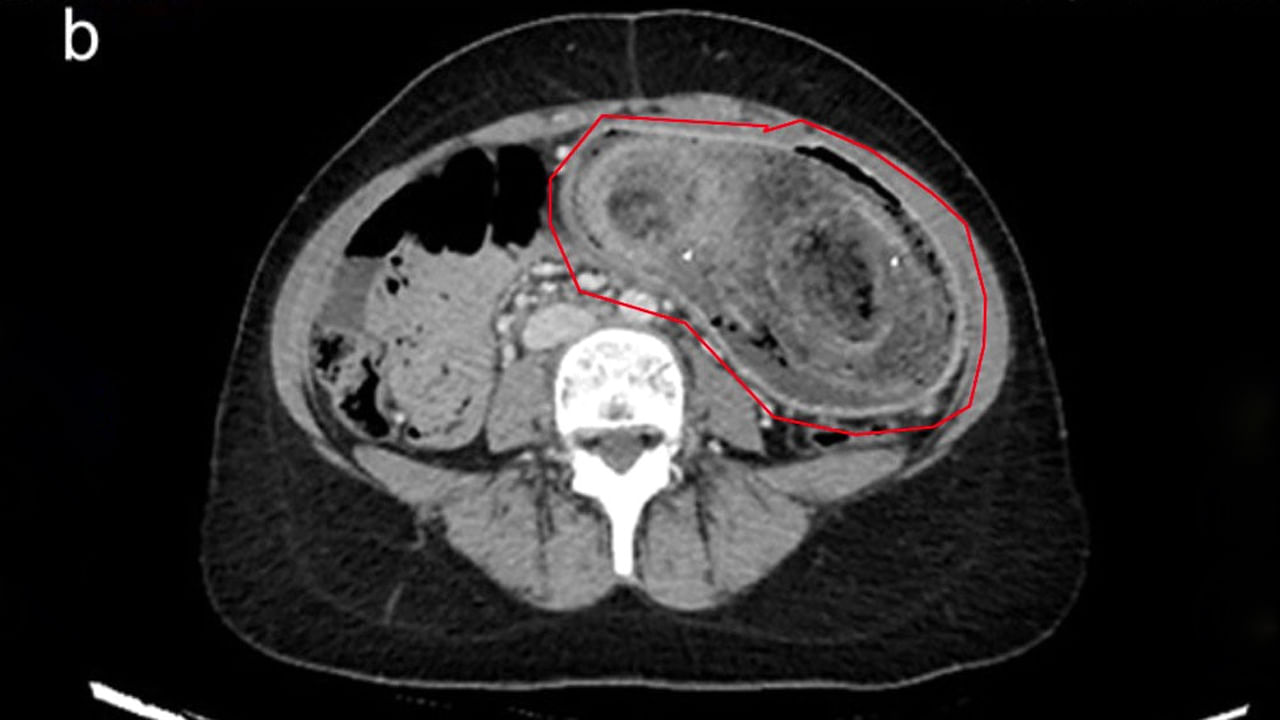

వివరాల్లోకి వెళ్తే.. 17 ఏళ్ల యువతి కడుపులో ఓ పెద్ద వెంట్రుకల ముద్దను చూసి వైద్యులు షాక్ అయ్యారు. కడుపునొప్పితో బాధపడటమే కాకుండా.. పదేపదే వాంతులు చేసుకుంటుండటంతో ఆమెను హుటాహుటిన ఆస్పత్రికి తరలించారు. ఇక చికిత్స చేసిన డాక్టర్లు.. ఆమెకు ‘పికా’ అనే వ్యాధి ఉన్నట్టు గుర్తించారు. ఆహారంగా కానివి తినాలనిపించే కోరిక.. ఈ వ్యాధిగ్రస్తులకు ఉంటుందట.

ఫలితంగా ఆ యువతి చాలా సంవత్సరాలుగా జుట్టును తినేది. డాక్టర్లు పరీక్షలు చేయగా.. ఆమె పొత్తికడుపులో ఉబ్బి కనిపించింది. ఆ ప్రదేశంలో వెంట్రుకల ముద్ద ఉన్నట్టు గుర్తించారు. ఆపై ఎండోస్కోపిక్ ద్వారా దాన్ని తొలగించారు వైద్యులు. మూడు గంటల పాటు ఈ శస్త్రచికిత్స జరిగింది. కాగా, చికిత్స చేసిన నాలుగు రోజుల తర్వాత ఆమెను డిశ్చార్జ్ చేయగా.. ఆ తర్వాత మానసిక నిపుణులతో కౌన్సిలింగ్ ఇప్పించారు.